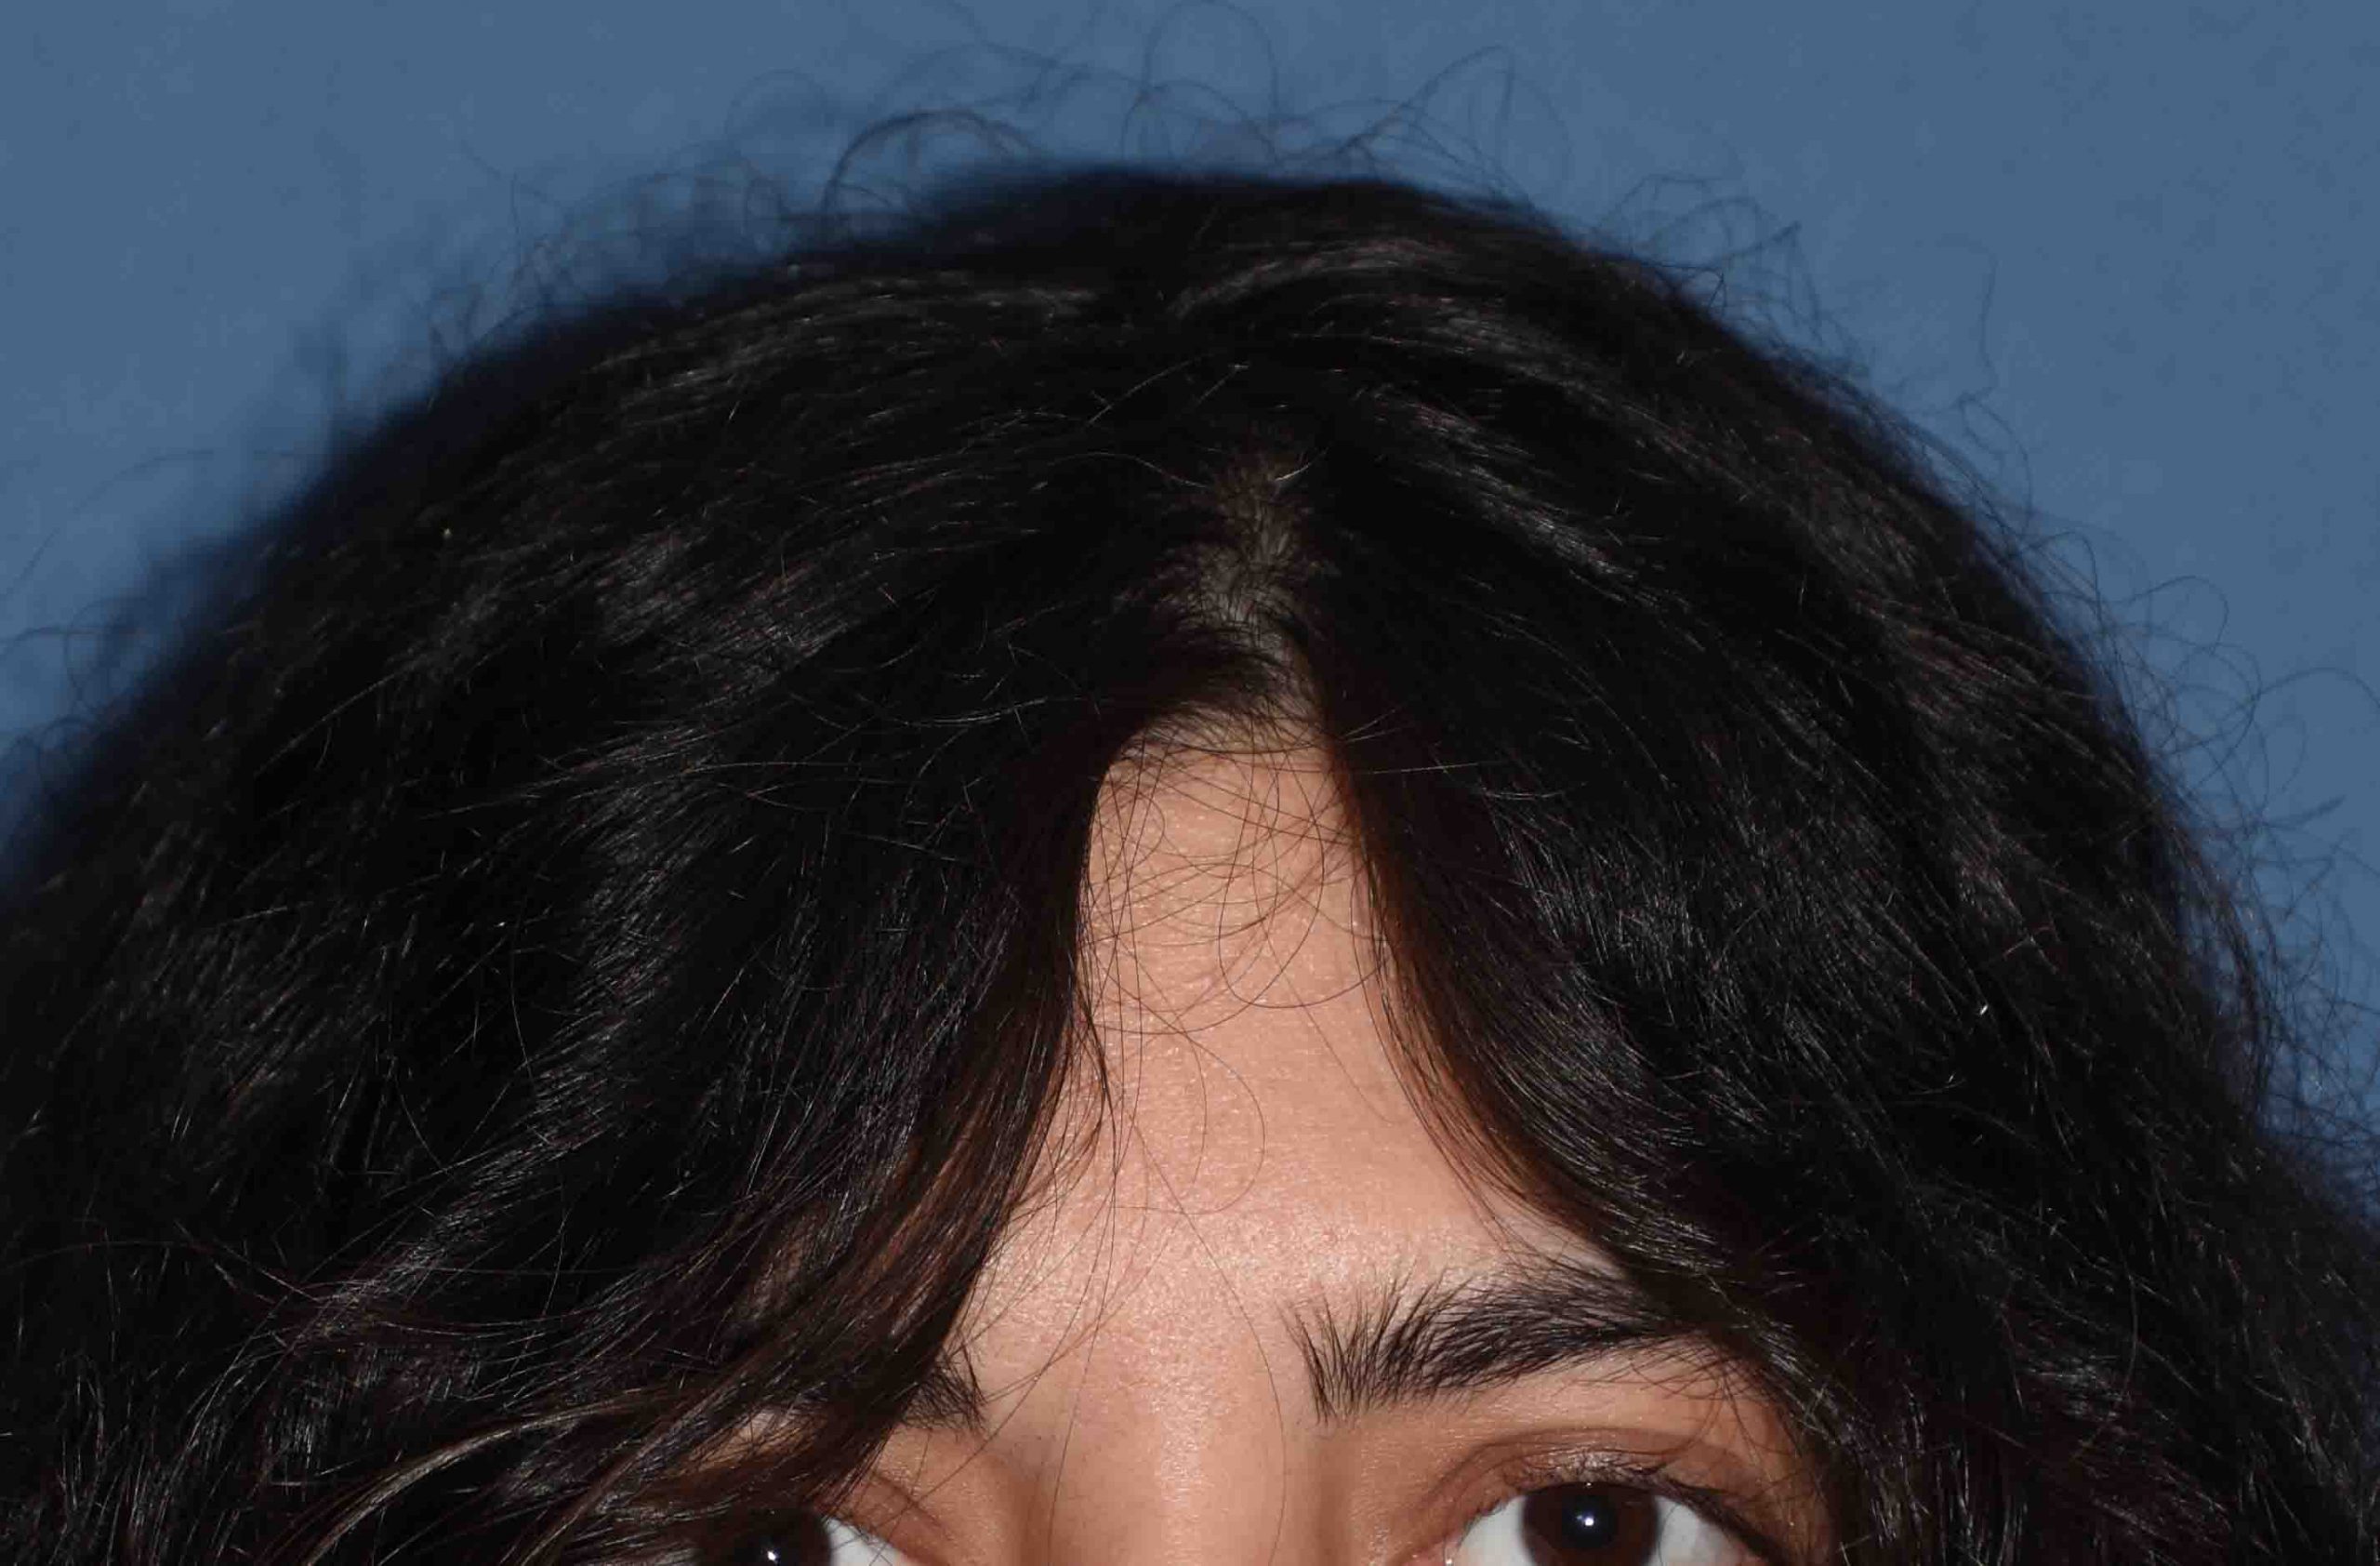

Patient 123

Desire for additional skull augmentation after a prior PMMA bone cement placement on the back of her head.

Placement of a custom skull implant to supplement her prior bone cement augmentation for an overall greater skull enhancement effect.